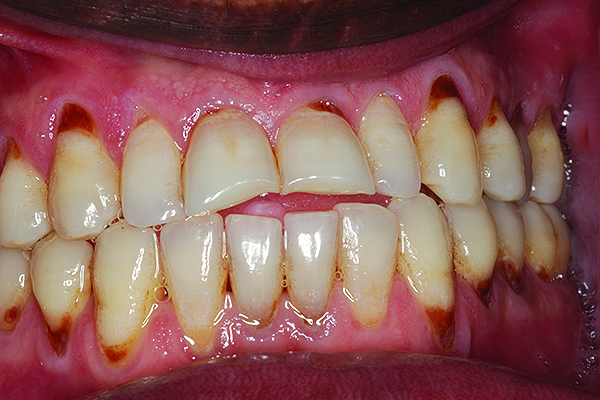

Fig 4. Periodontal disease in a patient with halitosis.

Figure 4

A rotten egg or cabbage smell is indicative of VSC being the main cause of halitosis. These compounds are usually associated with periodontal disease (Figure 3 and Figure 4) and/or tongue coating. Patients suffering from periodontitis or peri-implantitis require professional periodontal treatment in order to eliminate periodontal pathogens.5 Following a professional scaling and root planing appointment, Gram-negative anaerobic bacteria responsible for causing periodontal disease and producing VSC are reduced.5 This, in turn, encourages repopulation with Gram-positive cocci and bacterial rods that are associated with oral health.